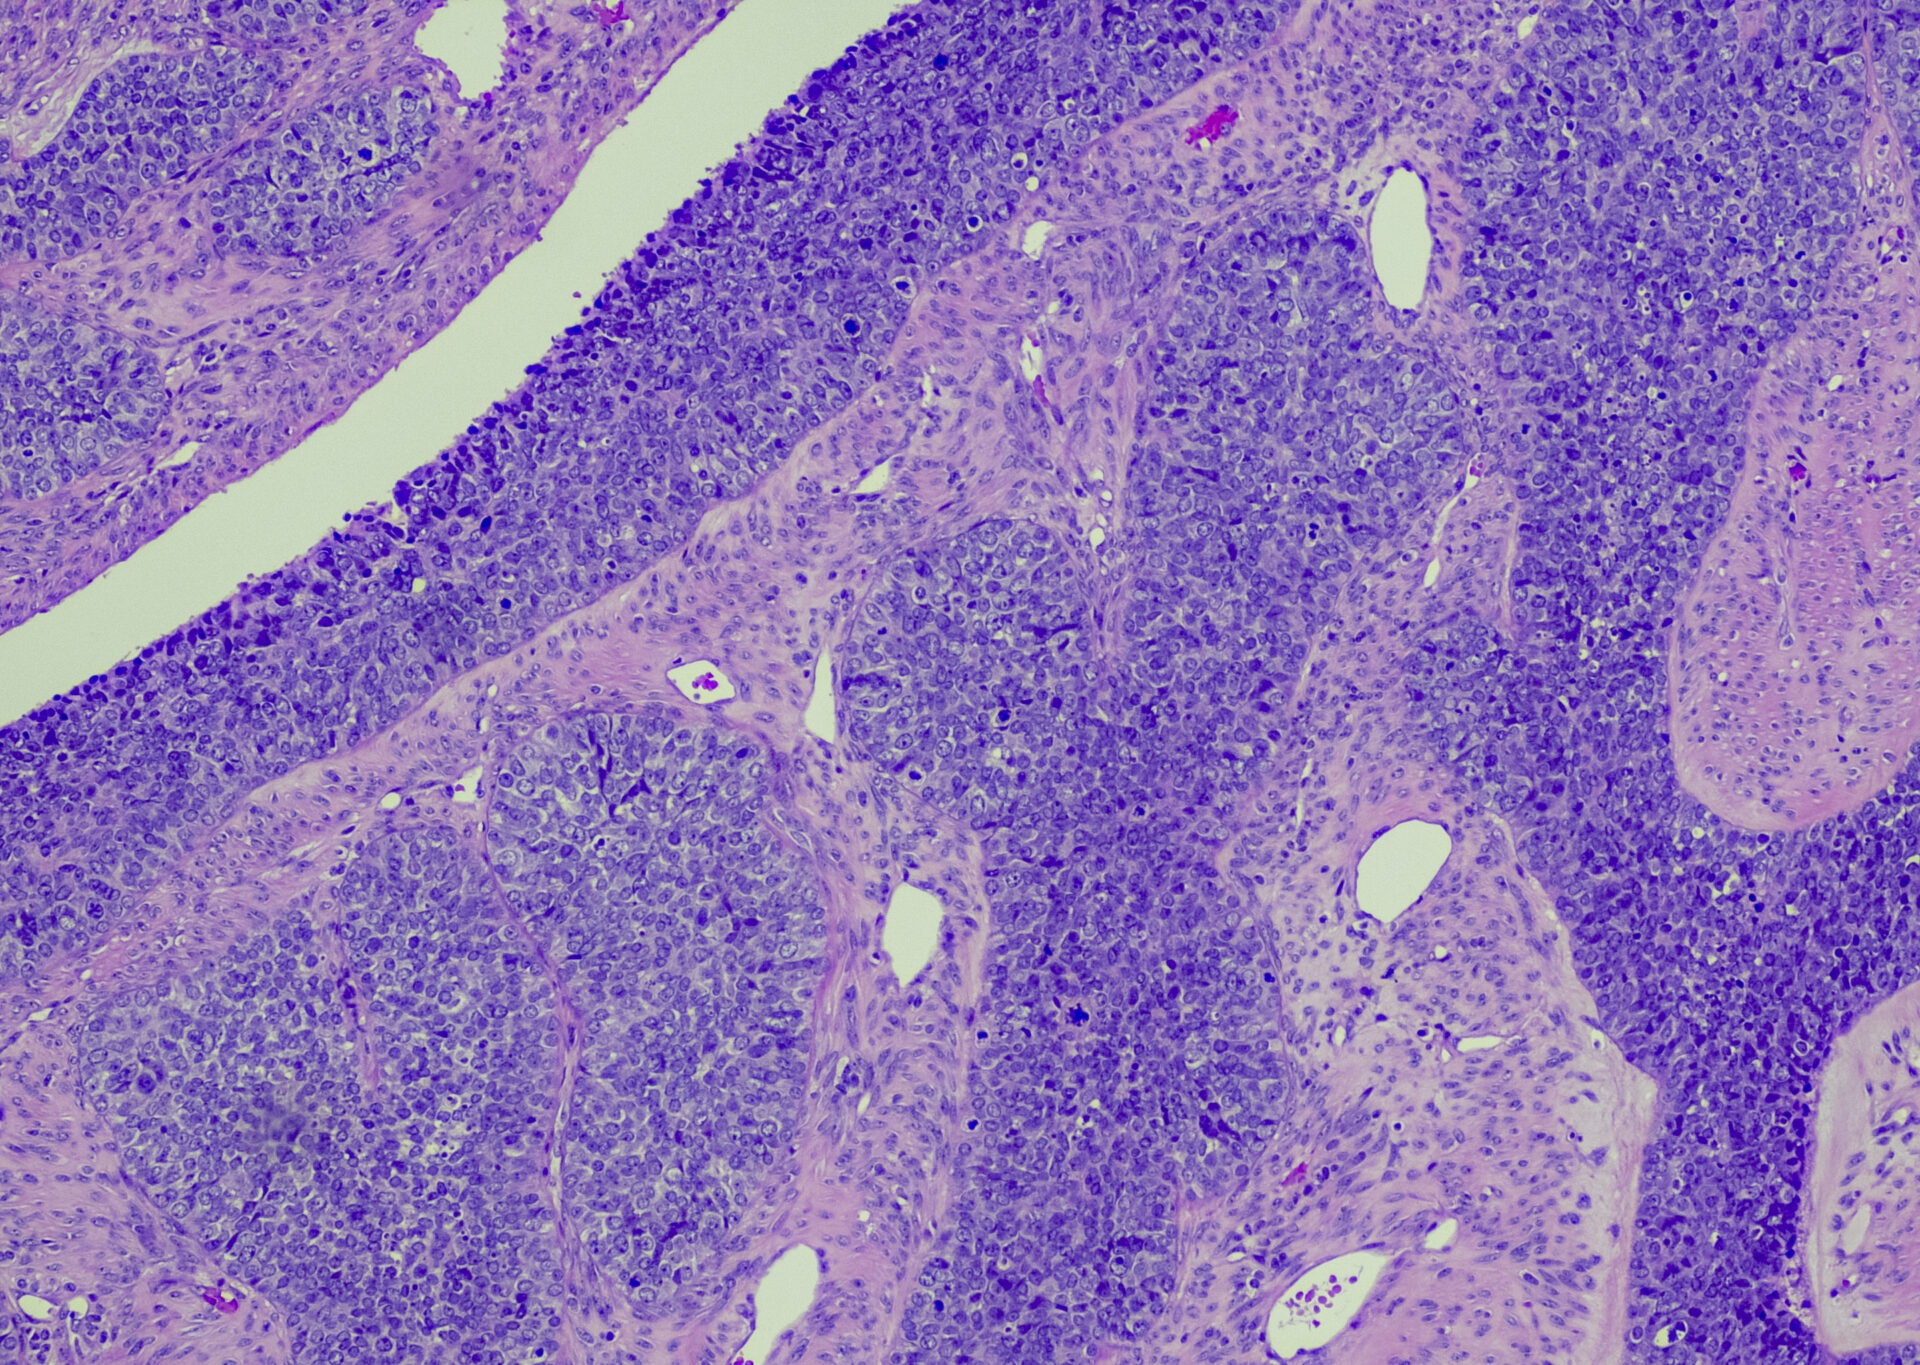

Die Standardbehandlung neu diagnostizierter fortgeschrittener Ovarialkarzinome besteht aus einer zytoreduktiven Operation, gefolgt von einer platinbasierten Chemotherapie mit oder ohne Bevacizumab. Eine Erhaltungstherapie mit PARP-Inhibitoren und Olaparib-Bevacizumab hat kürzlich gezeigt, dass sie das progressionsfreie Überleben in der Erstlinientherapie deutlich verbessert.